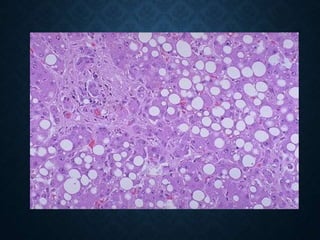

Steatosis hepatis

HISTOLOGICALLY

• macrovesicular-macrovesicular fatty change

• small droplet-microvesicular

• diffuse

• zonal